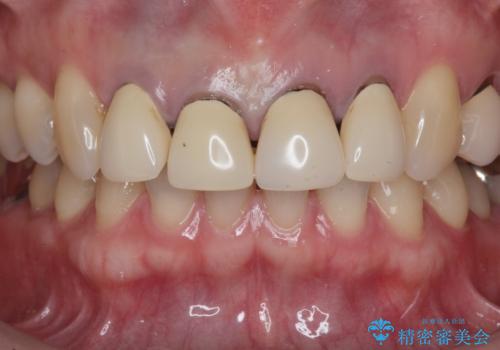

- 「黒ずみの前立つ前歯をやりかえ、きれいにしたい。」と希望され来院されました。

金属色の目立つ前装冠を除去し、発生していた小さな虫歯を丁寧に全て除去しジルコニアセラミッククラウンで審美的な前歯となるような治療を計画します。